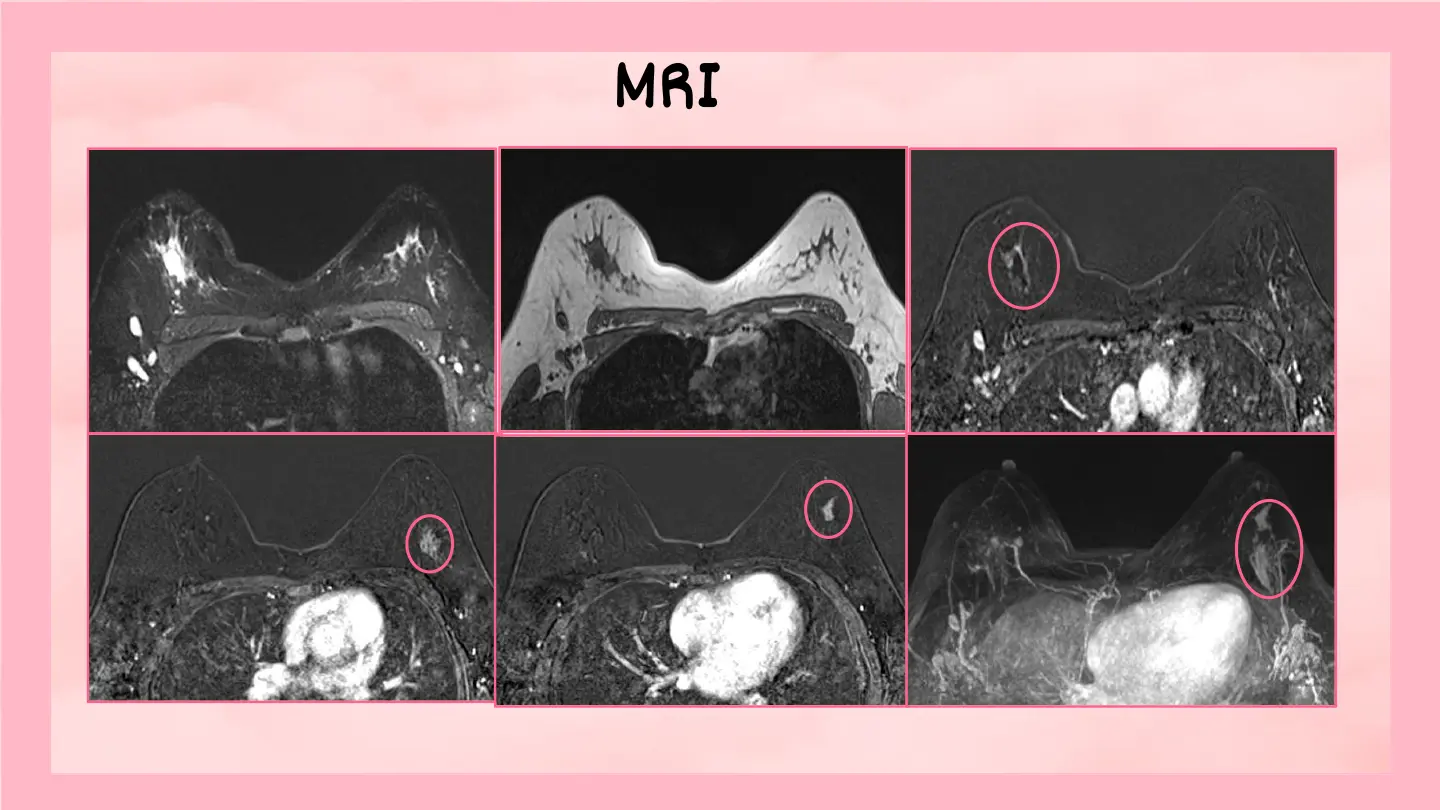

February 2026